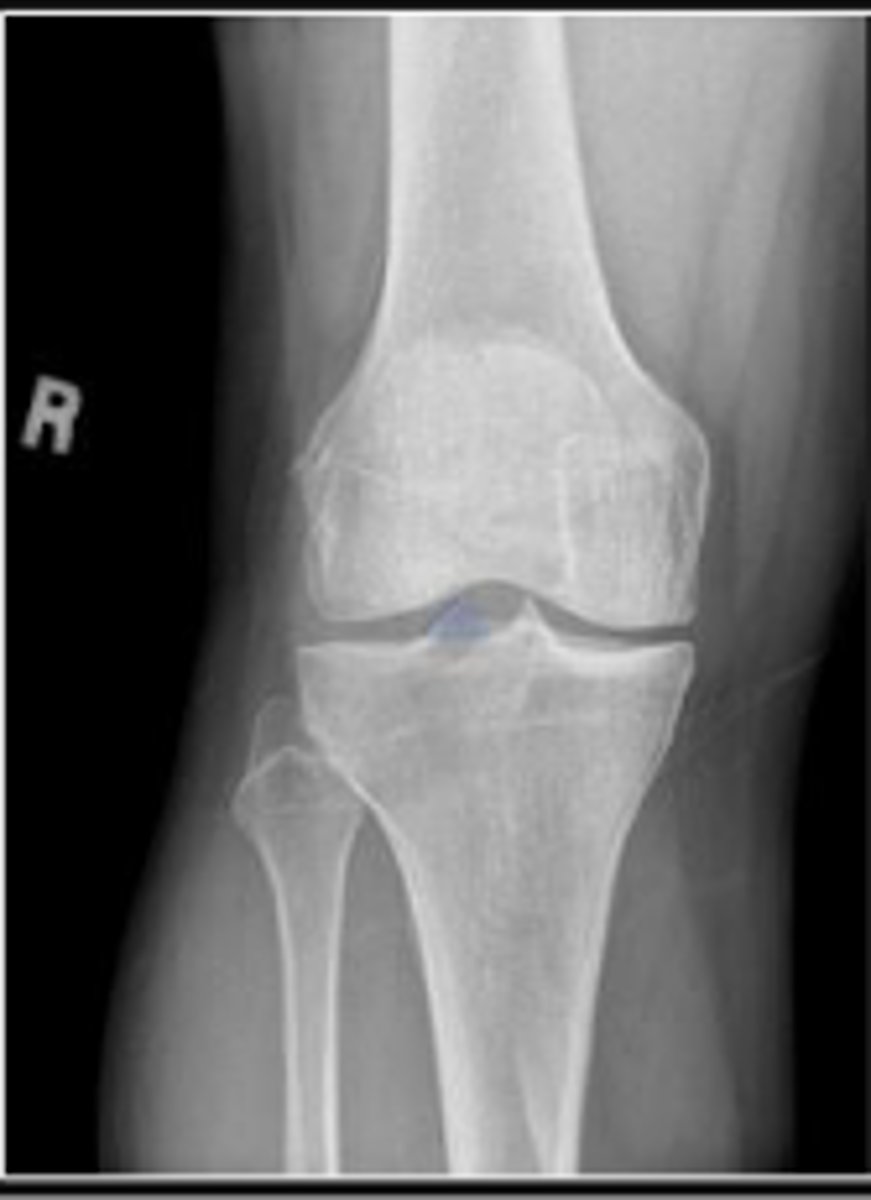

Right AP knee

What is the name of the radiographic view?